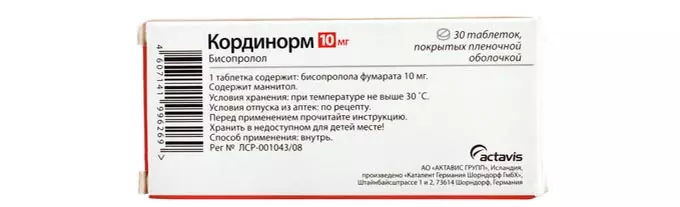

Состав препарата

Активно действующим компонентом Кординорма выступает бисопролола фумарат (bisoprolol), который присутствует в таблетках в двух вариациях:

- 5 мг.

- 10 мг.

В качестве дополнительных веществ в составе медикамента отмечаются:

- Манит.

- Макрогол.

- Гипромеллоза.

- Магния стеарат.

- Титана диоксид.

- Натрия кроскармеллоза.

Стоимость и форма выпуска

Кординорм производится в виде таблеток, имеющие круглую конфигурацию и выпуклые стороны, покрытые защитной пленкой. На одной стороне пилюли присутствует насечка, а на другой обозначена буква «В», которая представлена в двух вариантах, в зависимости от количества активного компонента в 1 таблетке:

- В5 – одна таблетка содержит 5 мг бисопролола.

- В10 – одна таблетка имеет 10 мг бисопролола.

Срок годности лекарства составляет 2 года, при этом необходимо учитывать особенности его хранения:

- Для таблеток по 5 мг температура хранения не более 25 градусов.

- Для таблеток с дозировкой по 10 мг условия хранения не выше 30 градусов.

- Кординорм можно приобрести в аптеке только по рецепту врача.

Цена препарата варьируется от 67 до 269 рублей.